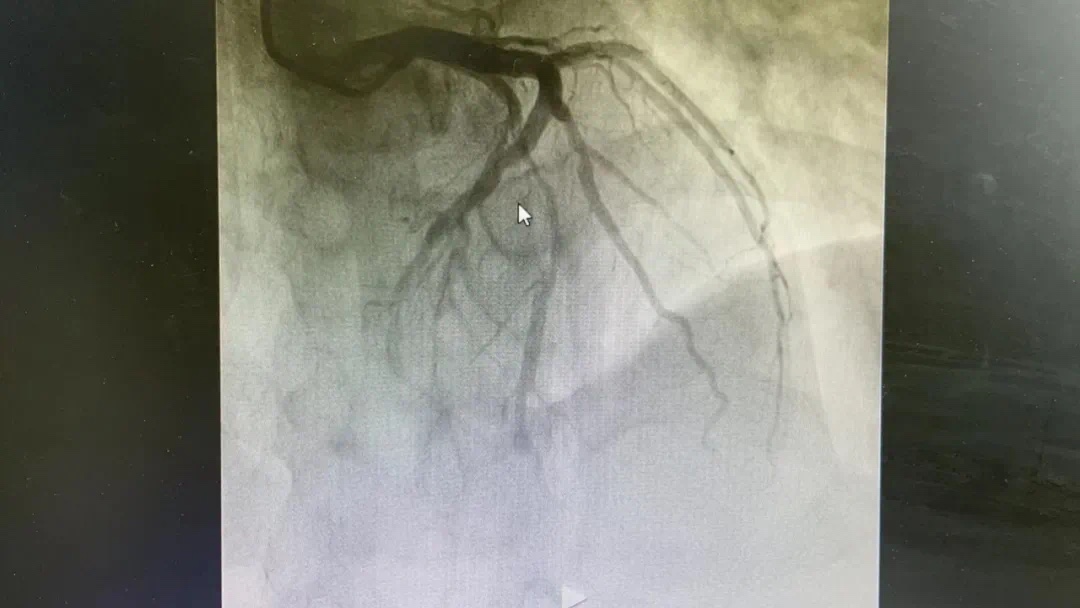

晚上21点15分,胸痛中心再次接到心内科病房胸痛患者王某的呼叫:高敏肌钙蛋白升高(提示心肌受损)。胸痛中心团队会诊后确诊急性心肌梗死,立即制定急诊冠脉介入治疗方案,并迅速启动导管室,成功完成血运重建,患者胸痛缓解。22点50分返回病房。

术前、术后图片如下